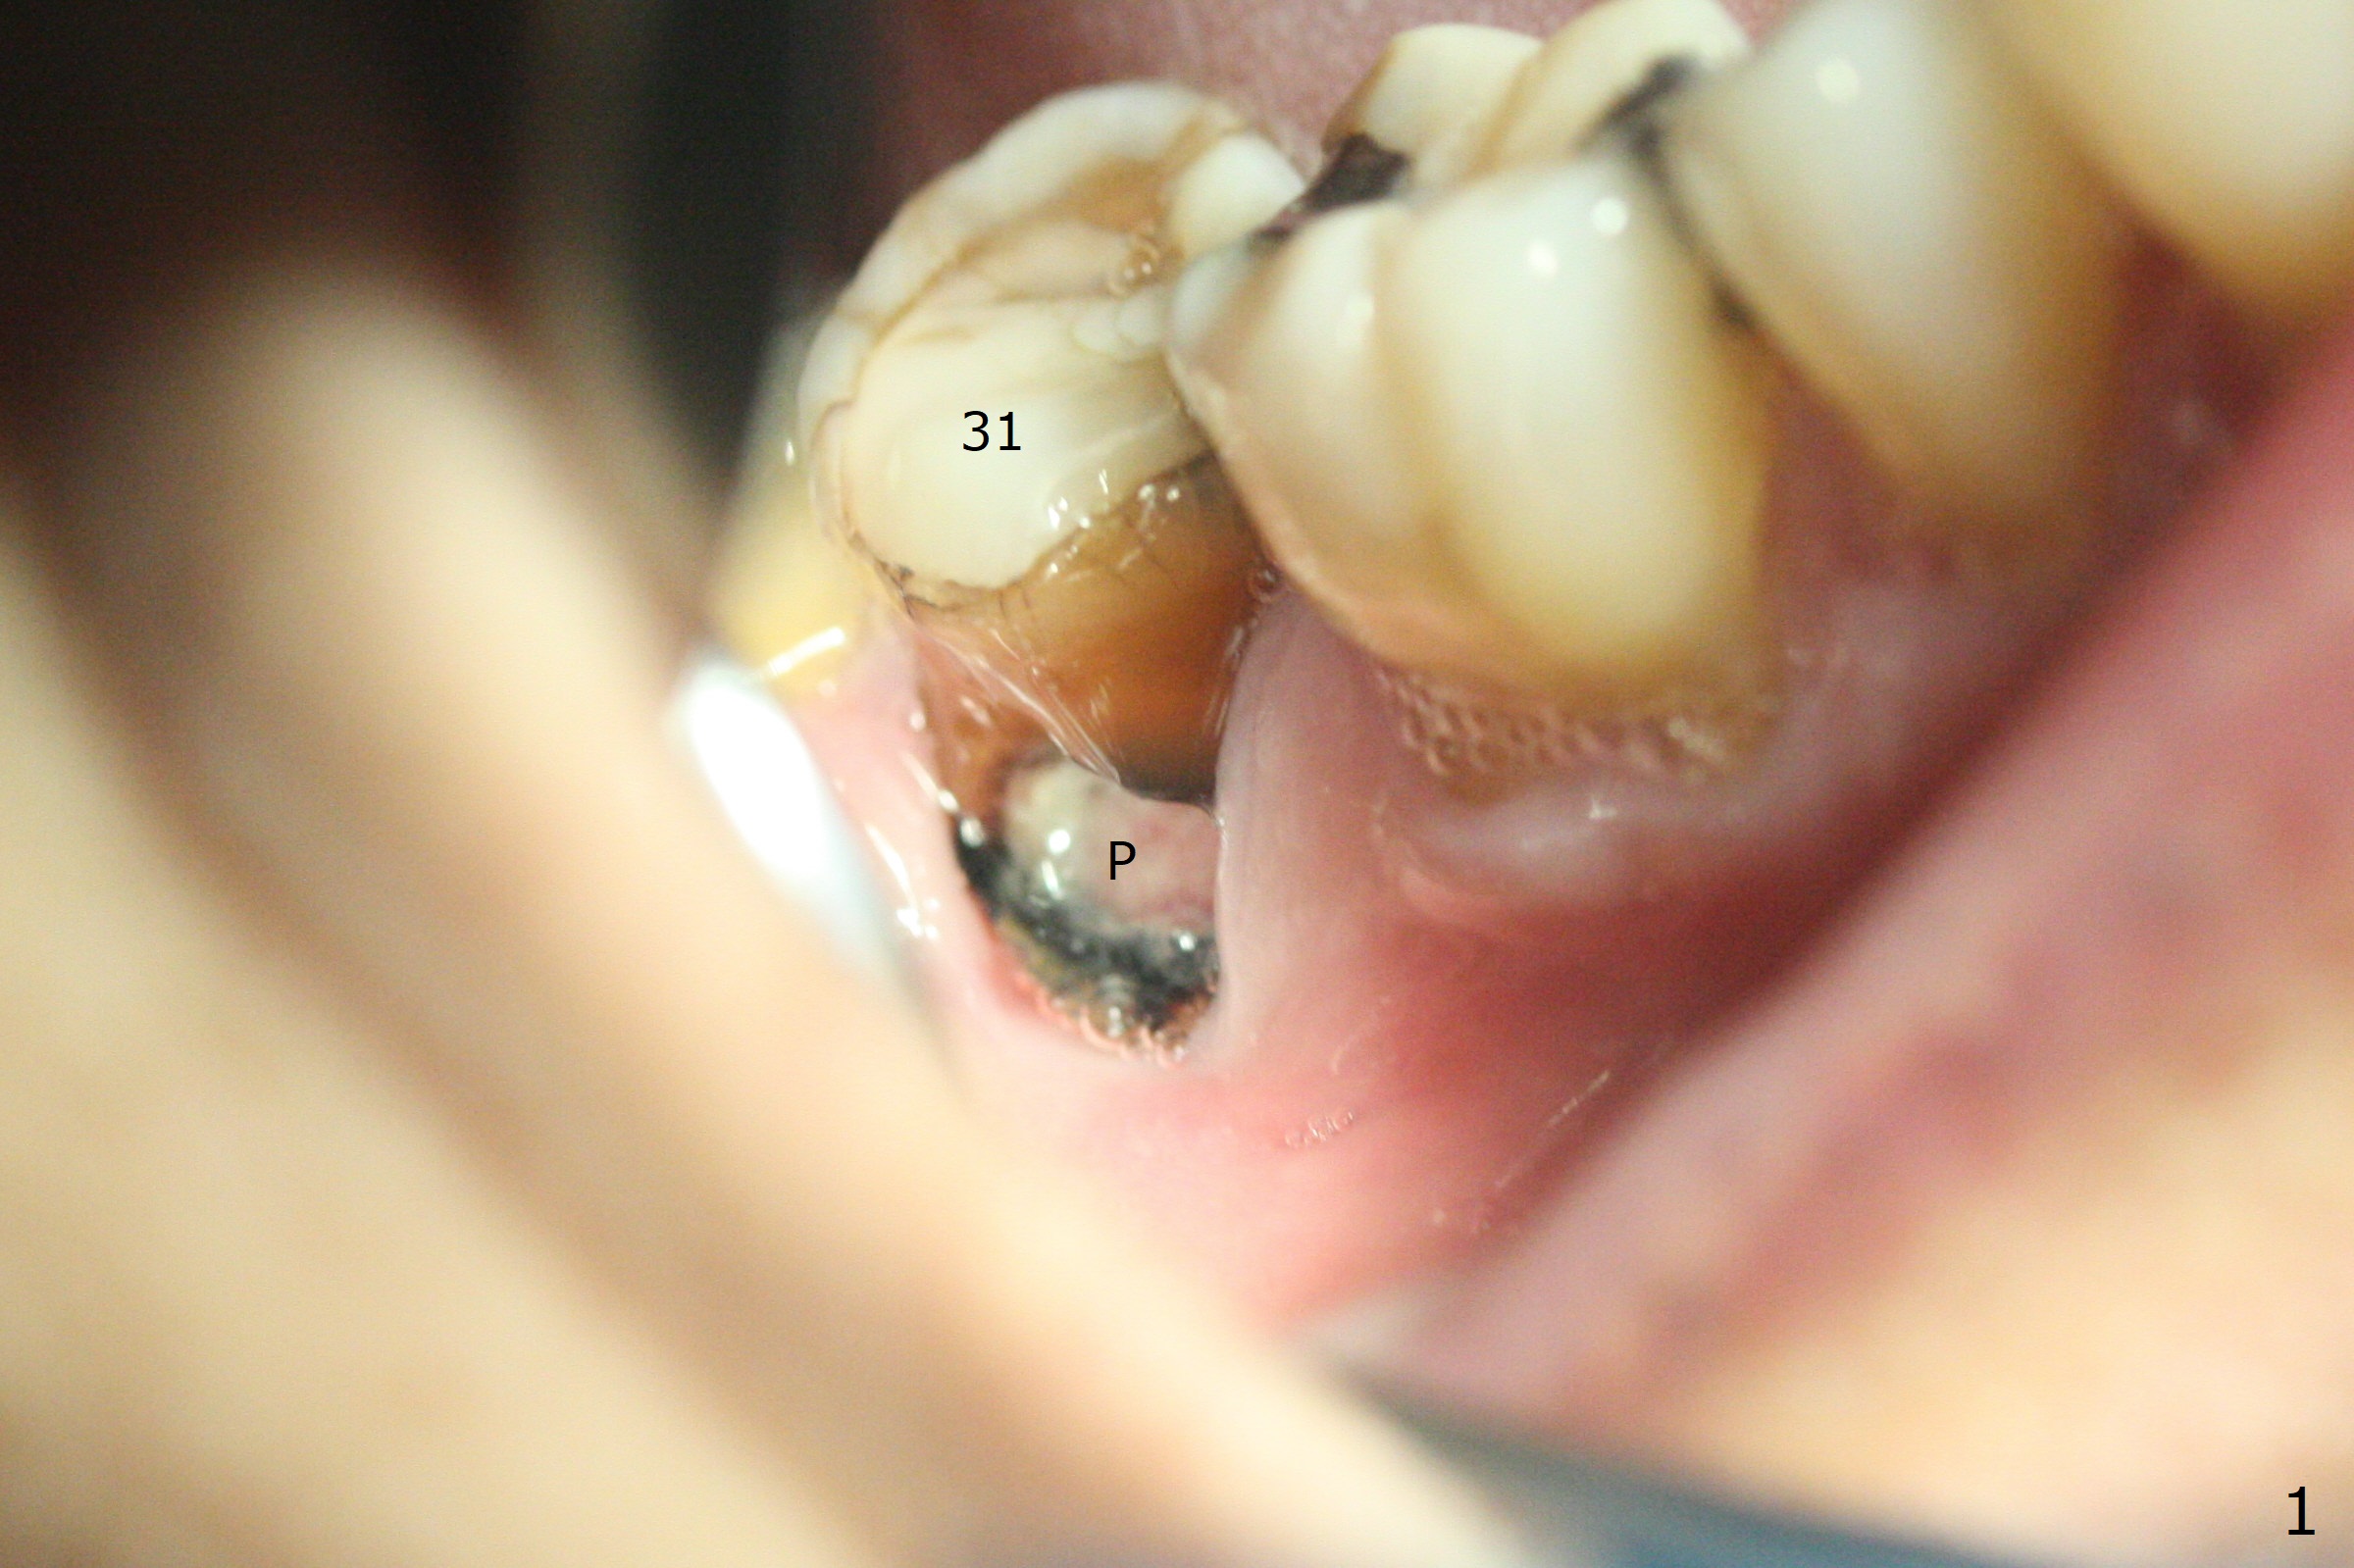

In fact the buccal gingival recession at #31 is asso-ciated with cervical caries perfor-ation (Fig.1 P). The debrided socket is packed with mine-ralized cortical: cance-llous mix (50:50) (better using mine-ralized cortical allograft (future particle size: 125μm – 850μm)) hydrated with ~ .25 ml of .3 mg/ml of rhPDGF-BB (one compo-nent of GEM21S, Fig.2,3). It is extremely difficult to close the socket opening with buccal defect with Osteogen Plug, 12x12 mm BioXclude and 4-0 PGA suture (Fig.4). Acrylic dressing is unstable in spite of several reline (Fig.5 A). Its replace-ment is GEM Cap RCM (regenerative collagen membrane), 9-12 month resorption time, which will be fixed in place with Perio Glue. Watch Video. In fact, 2 pieces of the reline dislodge in the 1st 2 days postop, while the whole piece 3rd days postop. The patient feels better when the acrylic dressing is out. It appears that the bone graft does not fall out, according to phone visit during coronavirus outbreak. A third method to close the buccal defect is to make mesial and distal release incisions (Fig.6) and transfer the flaps (Fig.7). In fact the bone graft gets lost, revealed over phone. Immediate implant is the most secure method to keep the bone graft. PRF may be more retentive. The fourth way is to place Cytoplast, which is fixed with spacer and periodontal dressing.